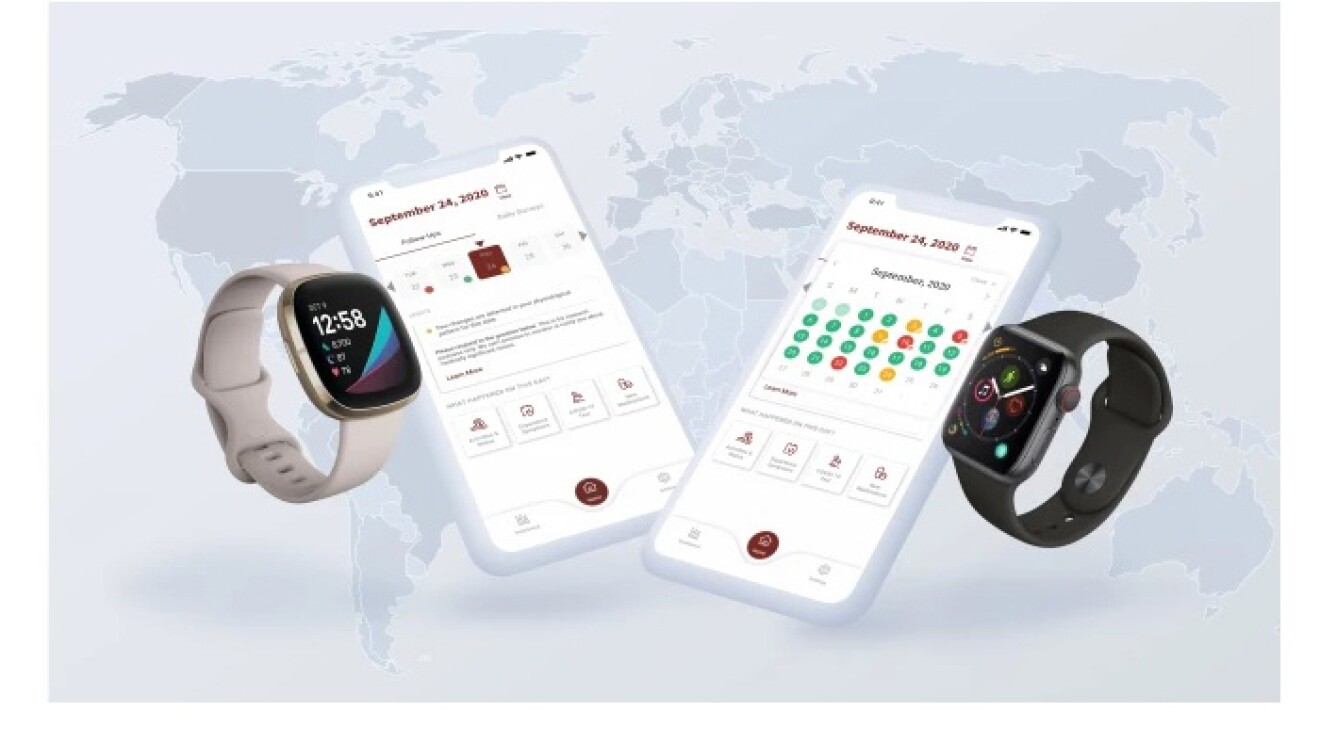

米スタンフォード大学医学部:スマートウォッチを使った診断用アラームシステムを開発

スタンフォード大学医学部ヘルスケア・イノベーション・ラボの研究者らは、COVID-19感染症と闘うための兆候をとらえるスマートウォッチ・アプリを開発しました。このアプリは、個人の安静時の心拍数と歩数の変化を検出するアルゴリズムを搭載しており、パイロット試験では新たに感染した人が症状を自覚する10日前に警告を発することに成功するなど、初期段階で良好な試験結果を得ています。

このアプリは次の研究段階に入っており、スタンフォード大学のチームは、COVID-19の兆候をリアルタイムで検出する能力を高めるため、1,000万人を目標に試験への参加者を募集しています。このスマートウォッチを利用した早期発見システムは、AWSプロフェッショナルサービスチームによるデータ処理パイプラインに関する支援を受けてAWS上に構築されました。

スタンフォード大学医学部 遺伝学分野教授 兼 学科長のMichael Snyder(マイケル・スナイダー)博士は、次のように述べています。「身に着けられるデバイスを用いた継続的な検診により、現在の検査の壁を克服するための拡張的な診断ソリューションが提供されること、また、より多くの研究者にデータへのアクセスを拡大することで、人々の健康を向上させる新たな発見に貢献できることを期待しています。今後もクラウドを活かして、可能性の限界に挑戦していきたいと思います」